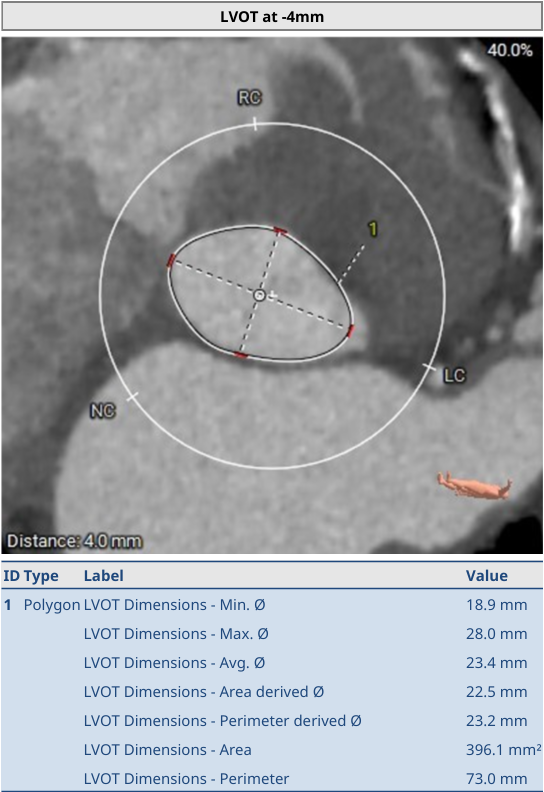

Annulus:23.4mm

LVOT-Avg:23.4mm

Min:18.9mm

AO-Avg:28.6mm